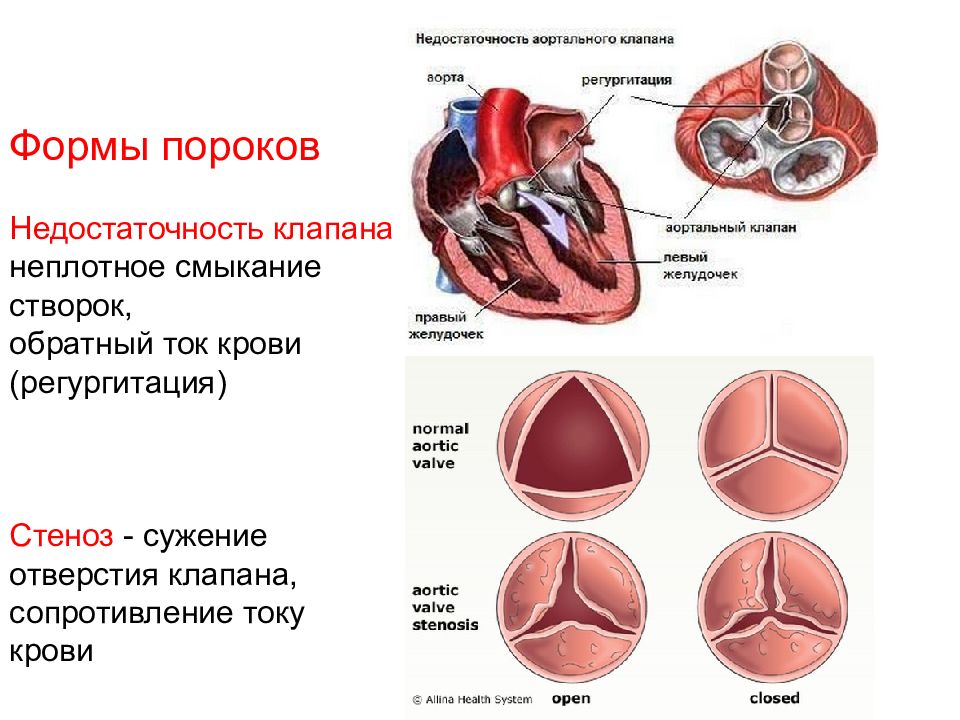

Пороки сердечно-сосудистой системы: виды и признаки